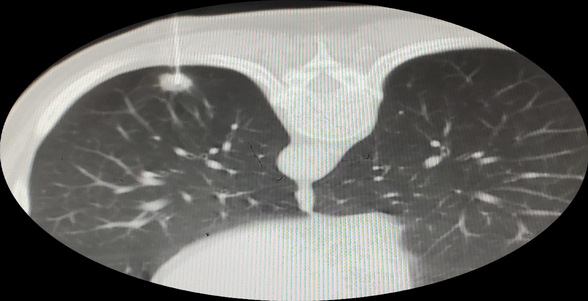

术中定位图像